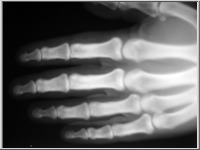

A képekre kattintva a röntgenfelvételek üveglemezeinek reprodukcióit, a kis képek jobb felső sarka melletti ikonokra klikkelve pedig az üveglemezeket védő, Gothard által feliratozott, a felvételek adatait tartalmazó borítékok reprodukcióit láthatjuk.

Az 1. sorszámú lemez elveszett, csak papírmásolat maradt fenn róla. A 25. és 26. sorszámú borítékok 2-2 felvételt tartalmaznak (itt a-val és b-vel jelölve), míg a 32. sorszámú lemez eltört, két darabban van.